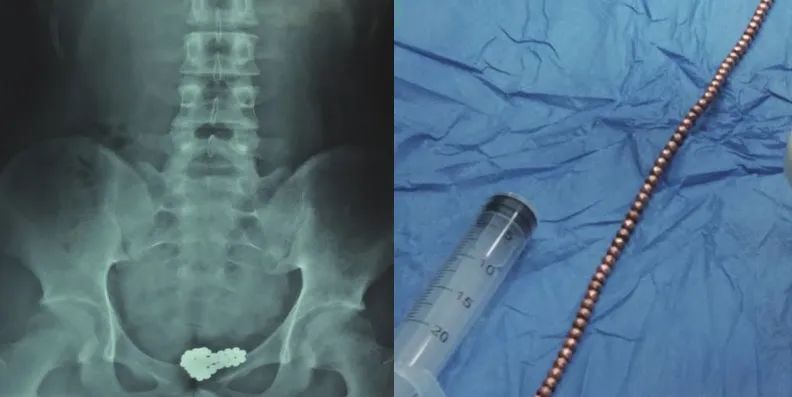

磁力珠丨参考文献10

膀胱镜下彩色的磁力珠丨参考文献10成人膀胱异物,多是为了获得性满足

[6]Liu ZH, Zhu XF, Zhou N. Retrieval of 159 magnetic balls from urinary bladder: a case report and literature review [J]. Urol Case Rep,2019,26:100975.